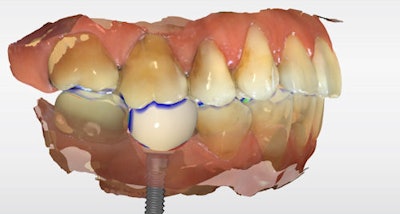

The definitive crown was then designed in CEREC software (Figure 4) using virtual articulation and occlusal analysis (Figure 5) and verified in a full-arch digital view for occlusal harmony (Figure 6). Milling was completed using CEREC Primemill with a Katana Zirconia One for Implant block, producing excellent marginal adaptation and lifelike translucency (Figure 7).

Figure 4: Digital crown design in CEREC software.